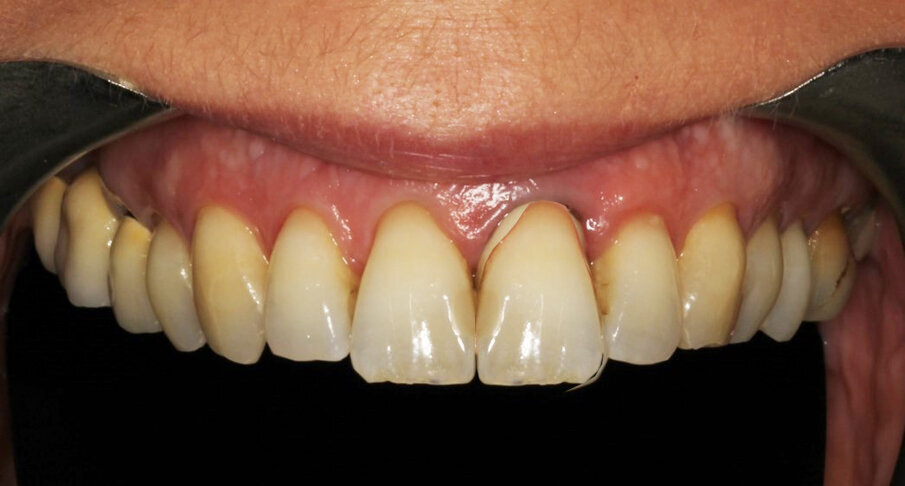

The photographic aesthetic evaluation showed that it would be very difficult to obtain symmetry in tooth shape and have good-looking and healthy soft tissue support at the same time. The patient’s maximum smile exposed the gingival contours. In such cases, it may be wise to consider also the possibility of altering the anatomy of the contralateral tooth with, for example, a ceramic veneer and discuss outcomes with the patient before finalising the treatment plan. This can be evaluated by performing the cut/copy/flip/paste sequence in reverse (Fig. 7). Together with the patient, it was decided to start performing the best possible replacement of the maxillary left central incisor and evaluate at an advanced stage with a temporary crown on the implant and mature, conditioned tissue whether to add a veneer to the maxillary right central incisor.

Tissue conditioning

As evidenced by the aesthetic analysis before treatment, it was clear that symmetry with the contralateral incisor would be impossible. The implant was placed slightly distal because the distal papilla normally has a narrower mesiodistal basis than the central papilla. The tissue volume augmentation helped to obtain the necessary quantity of gingiva to shape nice papillae, leaving a minimal gap. The soft tissue architecture was conditioned (Fig. 32) by adding composite to the temporary crown and grinding material where necessary until the prosthodontist and the patient felt an optimal result had been achieved.